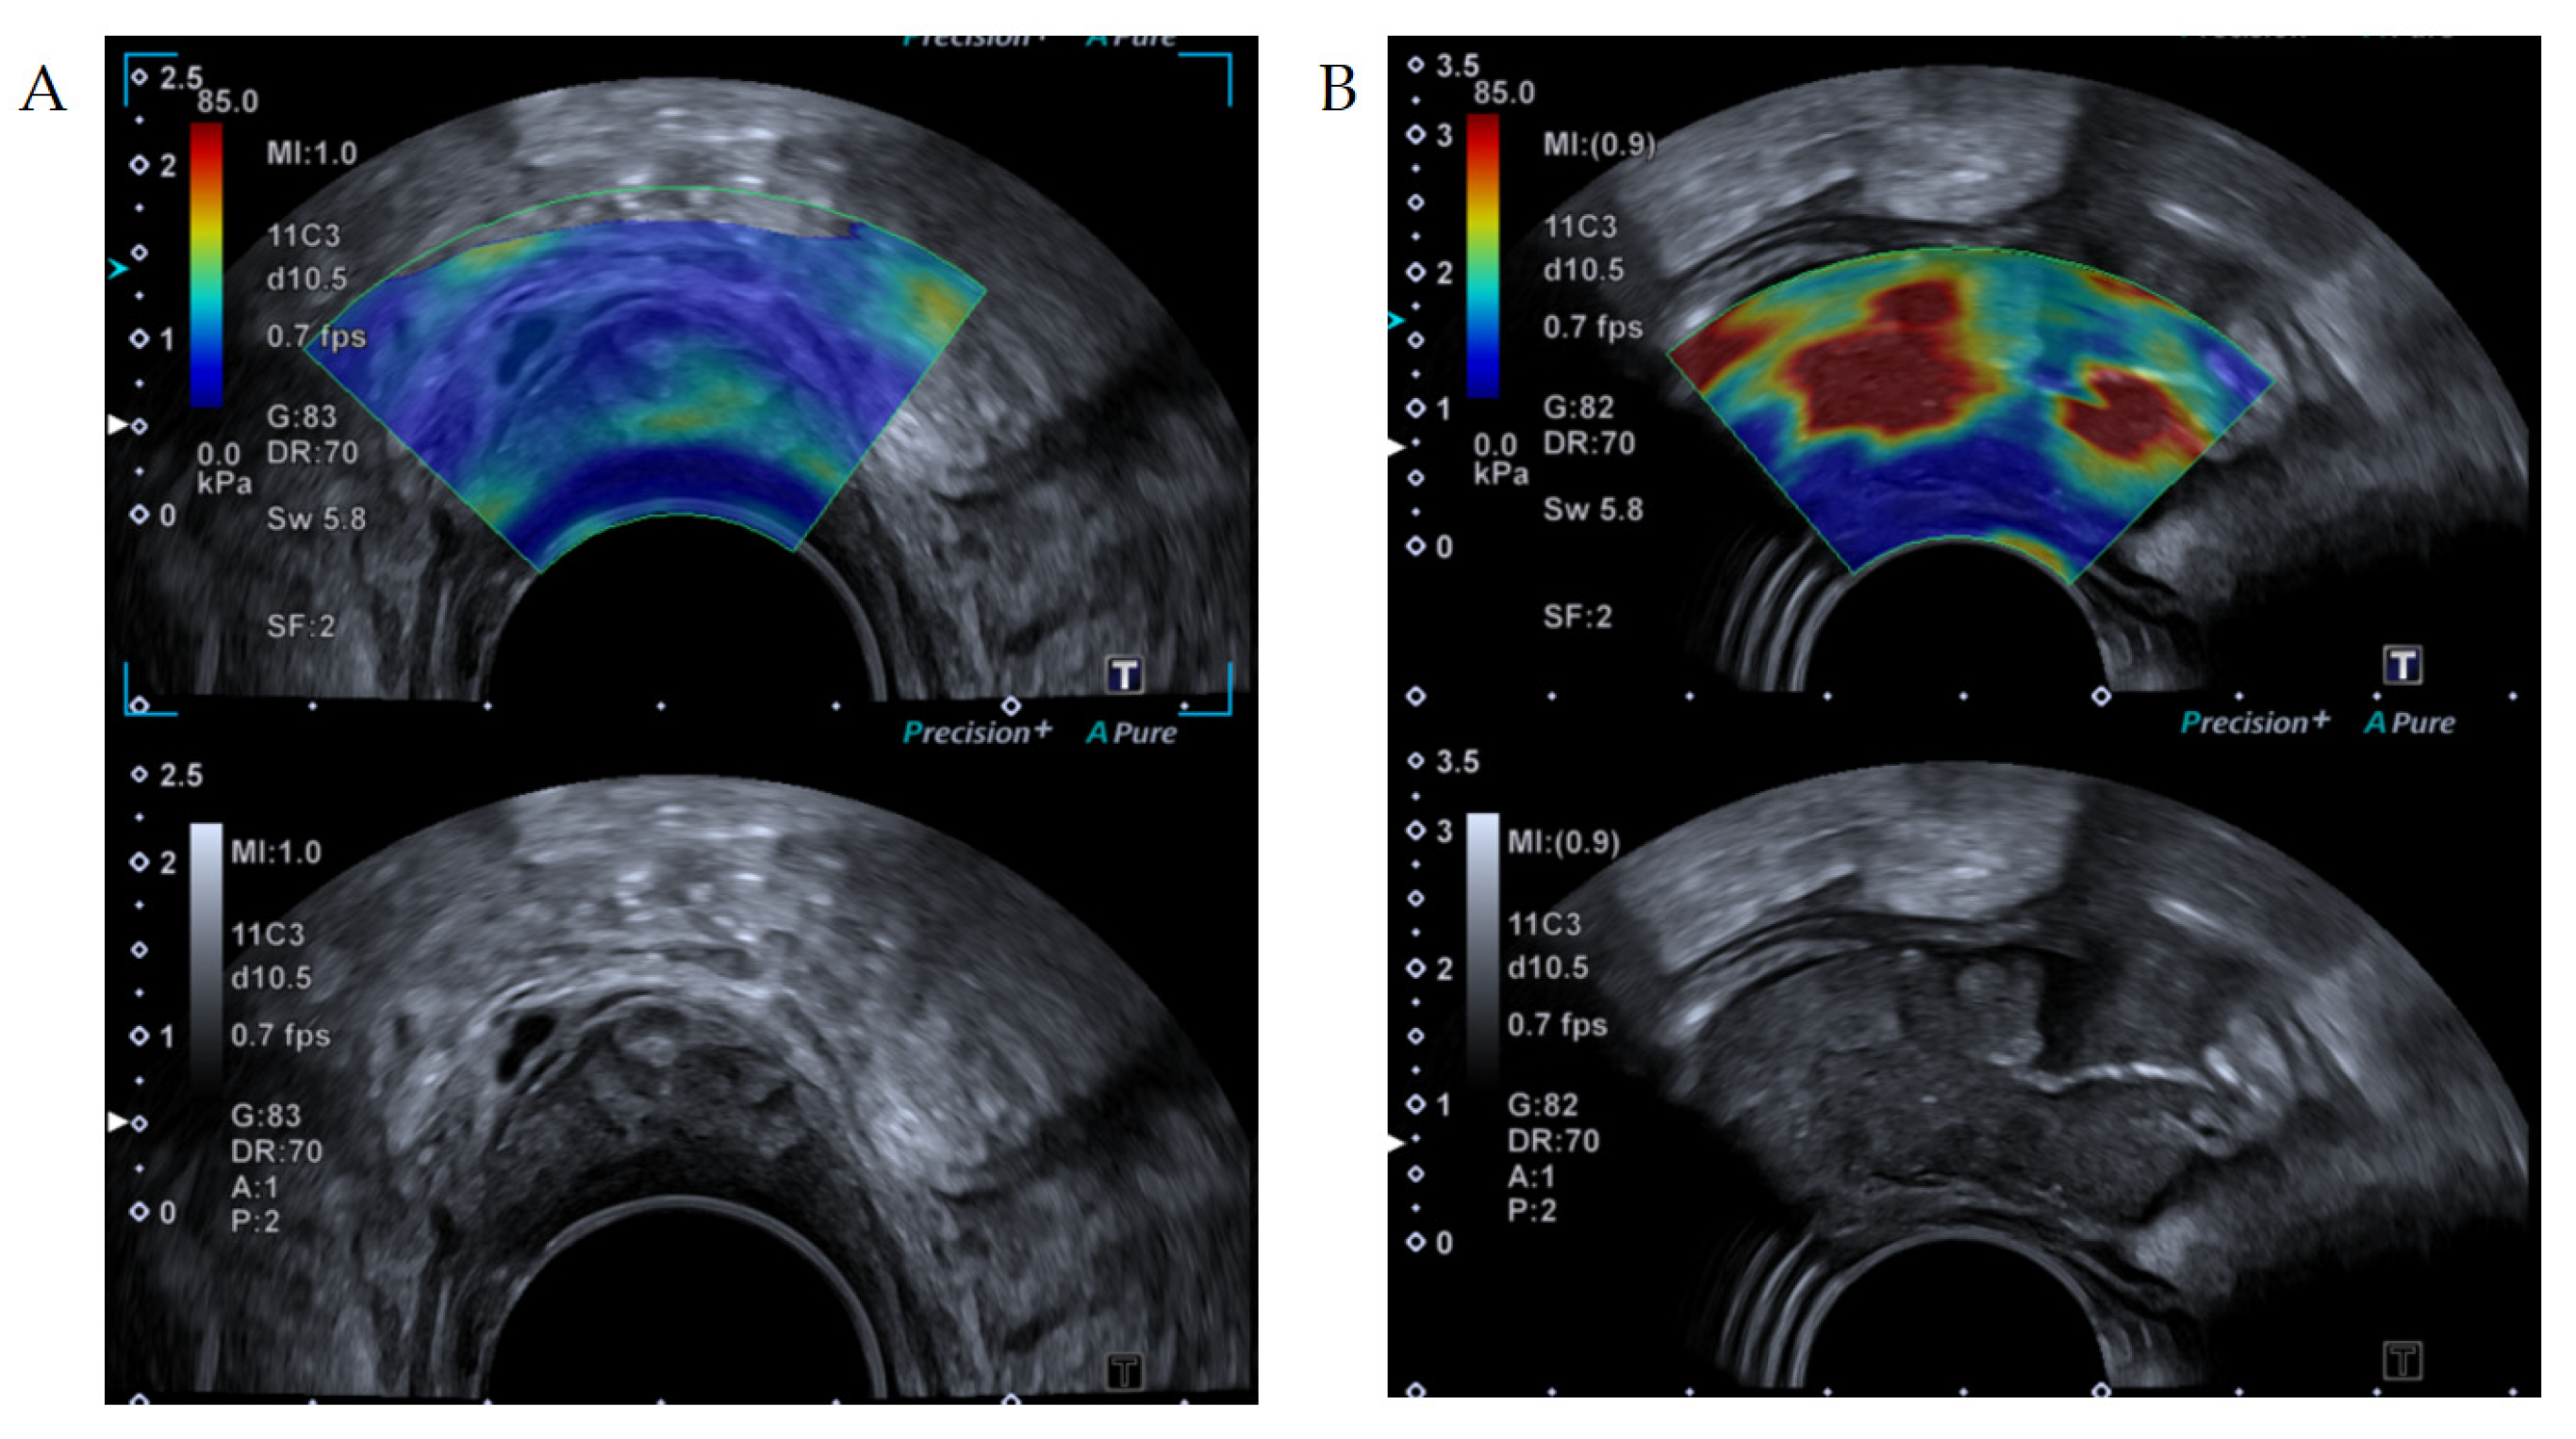

Figure 1.

Shear wave elastography images of an (A) adenoma and a (B) adenocarcinoma. Upper image shows the elastogram superimposed with a B-mode image. Bottom image is the corresponding B-mode ultrasound image allowing the examiner to place the region of interest within the tumor area. (A): The elastogram shows soft values (blue and green colors). (B): Adenocarcinoma with high elastography values (red colors).